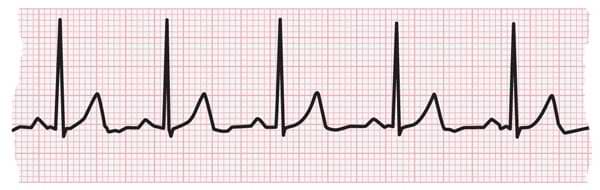

- Tachycardias are usually diagnosed by doing an electrocardiogram (EKG).

EKG strip showing a normal heartbeat